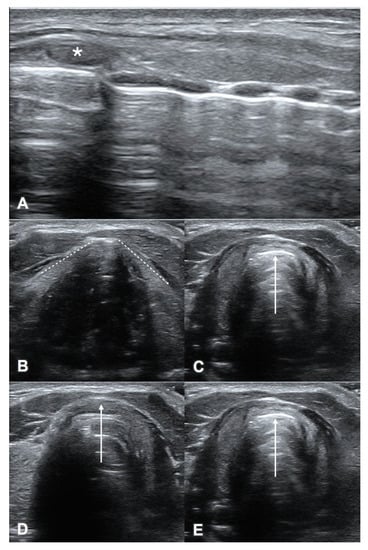

3. Probe Selection and Technique

4.1. Suprahyoid View

4.2. Thyrohyoid View

4.3. Thyroid View

4.4. Cricothyroid View

4.5. Suprasternal View